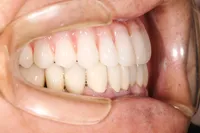

■治療前:上下顎 義歯での食事に満足されていない

■治療後:上下顎 複数本のインプラントを使い固定式で治療

| 主訴 | 現在義歯を使用しているが、しっかりと咬んでなんでもおいしく食事したい |

| 治療方法 | 上下顎 複数本のインプラントを使用しての治療 |

| 治療期間 | 約1年 |

| 通院回数等 | 約20回 |

| 費用 | 約600万円(税込) |

| リスク・副作用 | 術後の腫れ・痛み |